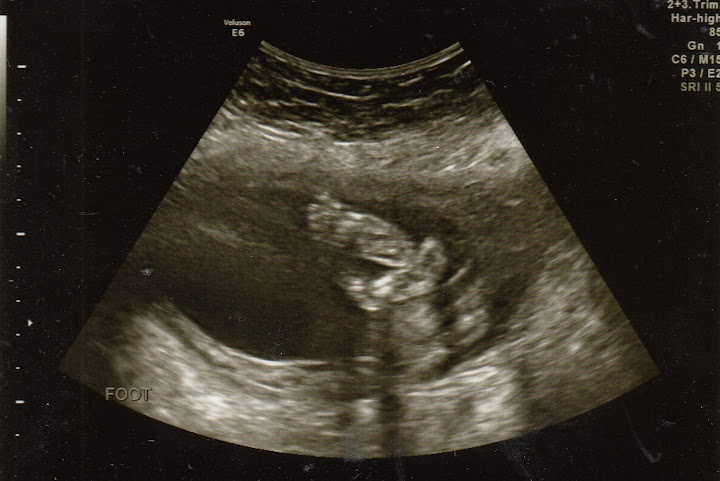

Here are her little feet. They look crossed to me.